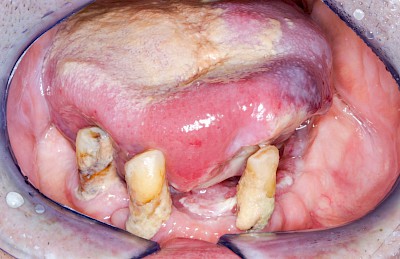

Schwellung & Geschwür

Gaumen, Wange & Zunge

Schwellungen oder Geschwüre sind in den meisten Fällen Krankheits-Zeichen, die mitunter sofortige Abklärung durch einen Zahnarzt erfordern.

- Lappenfibrom: z. B. bei mechanische Reizungen im Zusammenhang mit Zahnprothesen

Als Sonderform des Reizfibroms können bei Zahnprothesen in den Randbereichen selten am Gaumen, häufiger außen in den Umschlagfalten in Ober- und Unterkiefer auch lappenartige Auffaltungen (Lappenfibrome) beobachtet werden, die ebenfalls aufgrund eines mechanischen Dauerreizes entstehen. Alle diese Veränderungen sind in der Regel eher wenig schmerzhaft – auch wenn man darauf drückt. Hier sollte zeitnah mit einem Zahnarzt eine Abklärung erfolgen.